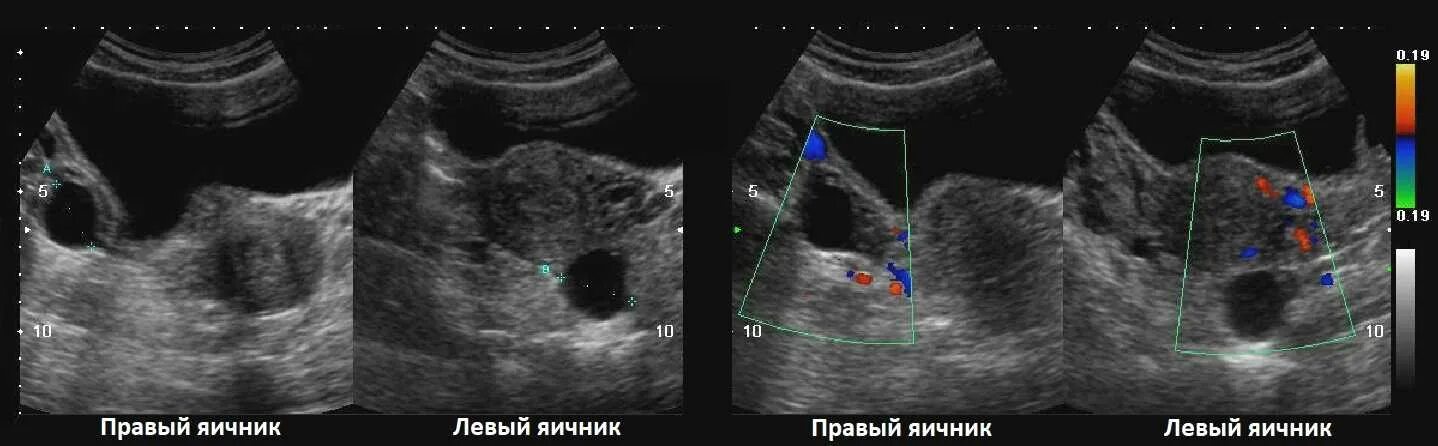

Как выглядит яичник